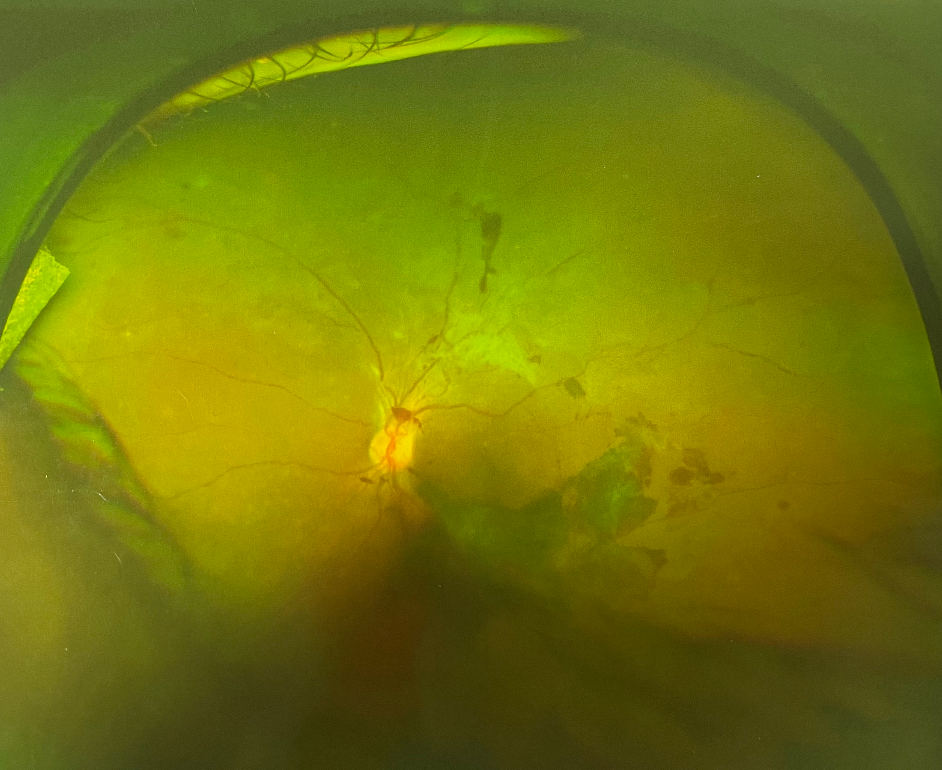

眼底出血什么原因?眼底出血通常是眼底視網(wǎng)膜血管的病變引起的。正常情況下,血液在人體的血管內(nèi)流動(dòng),不會(huì)溢出或滲出。如果正常人身體在不同年齡段發(fā)生變化或出現(xiàn)身體上的問題,眼睛也隨著出現(xiàn)問題;無論是眼睛局部的問題還是全身的病變,眼睛血管里流動(dòng)的血液就會(huì)溢出或滲出,出現(xiàn)在視網(wǎng)膜上,這就形成了眼底出血。那么眼底出血什么原因?

眼底出血什么原因?眼底出血的原因有很多,有些不是單一出現(xiàn)的,有的是高血壓,高血糖引起的,還有的是因?yàn)橐暰W(wǎng)膜靜脈阻塞,眼部炎癥,老年性的黃斑盤病變,身體出現(xiàn)血液變,血管瘤等等,這些都是眼底出血的一些原因。所以,一旦出現(xiàn)眼底出血的情況,一定要及時(shí)就醫(yī),以免耽誤病情。

眼底出血什么原因?1、視網(wǎng)膜靜脈阻塞

如果患有高血壓、動(dòng)脈硬化,也有可能會(huì)導(dǎo)致眼睛流血的情況出現(xiàn)。

眼底檢查可見靜脈阻塞區(qū)出現(xiàn)大量片狀或火焰狀出血,同時(shí)可伴視網(wǎng)膜水腫和滲出。如果視網(wǎng)膜靜脈分支阻塞,眼底出血一般在靜脈阻塞區(qū)局部,視網(wǎng)膜中央靜脈阻塞時(shí),眼底出血廣泛而嚴(yán)重。視網(wǎng)膜分支靜脈阻塞累及黃斑區(qū)或視網(wǎng)膜中央靜脈阻塞,患者可出現(xiàn)顯著的視力下降。

眼底出血什么原因?2、糖尿病視網(wǎng)膜病變

患者有糖尿病病史,有些糖尿病患者本人并不知曉,血糖檢查可明確診斷。糖尿病視網(wǎng)膜病變的眼底出血是逐漸發(fā)展的。早期僅表現(xiàn)為少量點(diǎn)狀出血,伴微血管瘤,隨病程進(jìn)展可出現(xiàn)點(diǎn)片狀出血和滲出。此時(shí)患者多無自覺癥狀,一旦病變進(jìn)展到增生期或出現(xiàn)黃斑水腫,患者可表現(xiàn)為視力下降。如果視網(wǎng)膜新生血管導(dǎo)致視網(wǎng)膜前大量出血或玻璃體出血,患者通常出現(xiàn)視力驟降,嚴(yán)重者僅可見手動(dòng)。

眼底出血什么原因?3、老年性黃斑變性

老年性濕性黃斑變性的眼底出血部位一般局限在黃斑區(qū),患者年齡多在50歲以上。臨床表現(xiàn)為突然的視力下降,以中心視力損害為主。OCT檢查可發(fā)現(xiàn)黃斑區(qū)視網(wǎng)膜下新生血管膜(CNV)。濕性黃斑變性晚期也可以出現(xiàn)大面積的視網(wǎng)膜下出血,甚至玻璃體出血,引起更嚴(yán)重的視力損害。

眼底出血什么原因?4、其它原因

血壓性視網(wǎng)膜病變、腎病性視網(wǎng)膜病變、血液病等全身性的疾病都有可能會(huì)讓眼睛流血。視網(wǎng)膜裂孔、眼外傷等眼病也可以導(dǎo)致眼底出血。